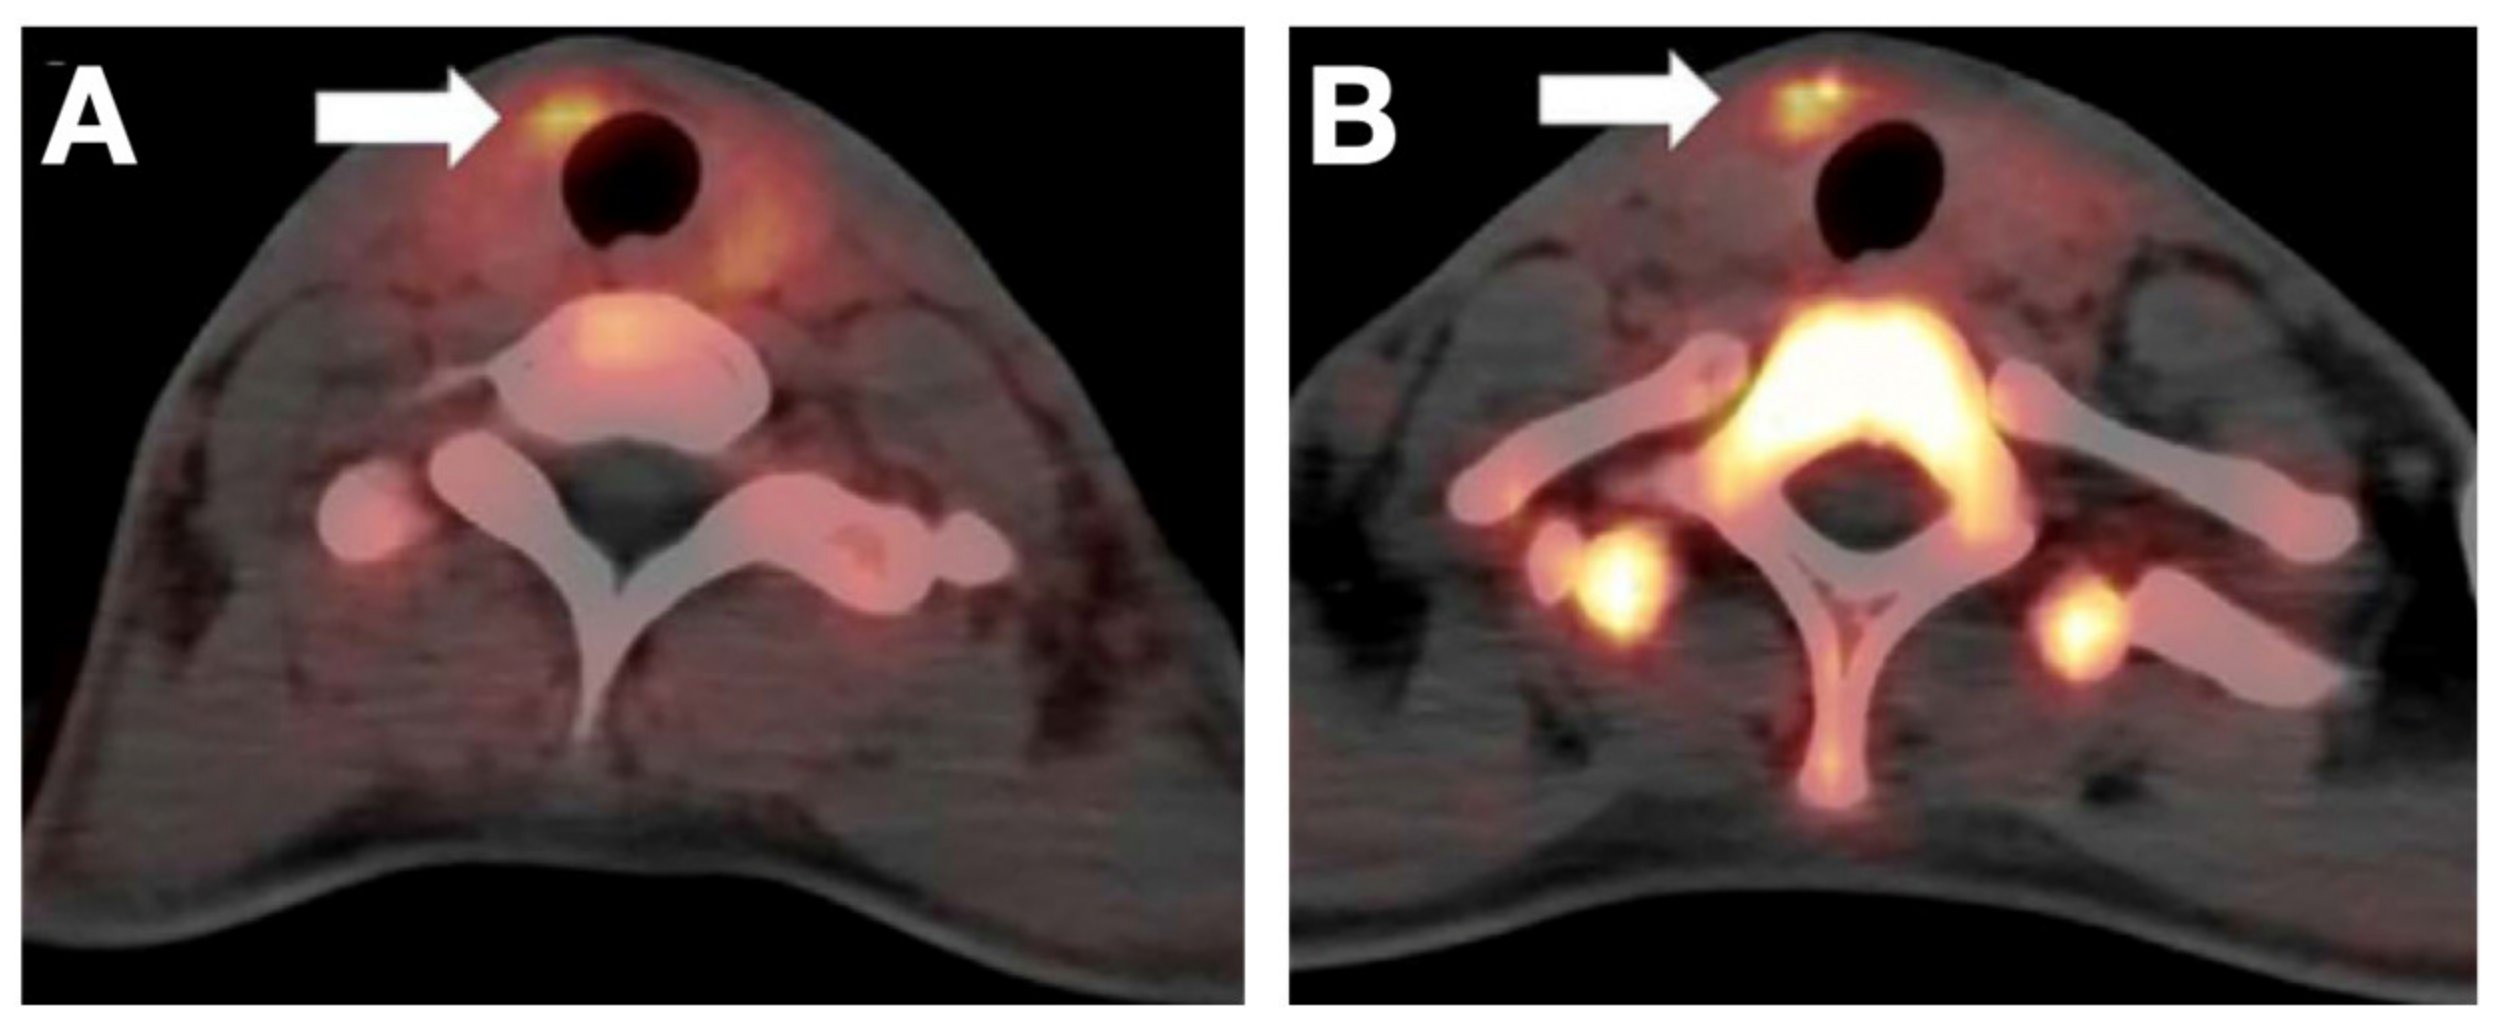

- Dittmann, M.; Carvalho, J.M.G.; Rahbar, K.; Schäfers, M.; Claesener, M.; Riemann, B.; Seifert, R. Incremental Diagnostic Value of [18F]Tetrafluoroborate PET-CT Compared to [131I]Iodine Scintigraphy in Recurrent Differentiated Thyroid Cancer. Eur. J. Nucl. Med. Mol. Imaging 2020, 47, 2639–2646. [Google Scholar] [CrossRef]

- Samnick, S.; Al-Momani, E.; Schmid, J.-S.; Mottok, A.; Buck, A.K.; Lapa, C. Initial Clinical Investigation of [18F]Tetrafluoroborate PET/CT in Comparison to [124I]Iodine PET/CT for Imaging Thyroid Cancer. Clin. Nucl. Med. 2018, 43, 162–167. [Google Scholar] [CrossRef]